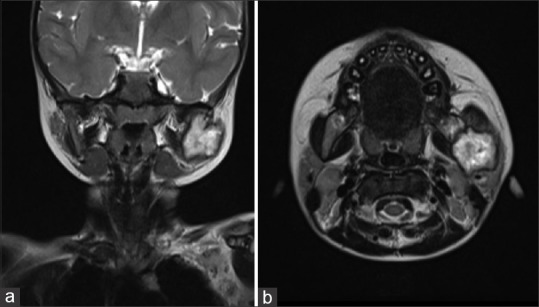

朗格汉斯细胞组织细胞增多症(LCH),也称为组织细胞增多症X或嗜酸性肉芽肿,是朗格汉斯细胞的一种局部或全身性异常克隆增殖性疾病。它具有广泛的临床表现,可发生在任何年龄组,以儿童和年轻人为主。这篇文章提出了一个罕见的病例LCH在一个2岁的女孩被暂时诊断为感染的颌骨不明病因。将临床、放射学和组织学特征与免疫组织化学分析相结合有助于得出LCH的明确诊断。口腔表现是大约5%-75% LCH病例中最早的表现,这强调了牙医在早期发现这种病变中的作用。由于朗格汉斯细胞病理浸润到各种系统,无数的临床光谱需要口腔诊断,然后进行全身扫描以检测任何系统累及。先进的靶向治疗可提高LCH患者的生存率和生活质量。

Langerhans cell histiocytosis (LCH), also called histiocytosis X or eosinophilic granuloma, is a local or systemic unusual clonal proliferative disorder of Langerhans cells. It has a wide spectrum of clinical presentations and can occur in any age group with predominance in children and young adults. This article presents a rare case of LCH in a 2-year-old girl child which was provisionally diagnosed as an infection of the jaw bone of unknown etiology. Correlating the clinical, radiologic, and histologic features with immunohistochemical analysis aided in arriving at a definitive diagnosis of LCH. Oral manifestations being the earliest presentation seen in around 5%-75% of LCH cases emphasize the role of a dentist in the early detection of this lesion. A myriad of clinical spectra due to pathologic infiltration of Langerhans cells into various systems necessitates oral diagnosis to be followed by a full body scan to detect any systemic involvement. Advanced targeted therapies can improve the survival rate and quality of life in patients with LCH.